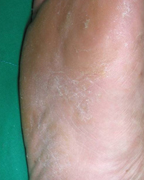

2단계: 진행된 상태

초기 증상을 방치하면 아래의 증상으로 진행됩니다.

- 발가락 사이의 피부가 점점 더 많이 벗겨지고 각질층이 두꺼워집니다.

- 발바닥까지 간지러움과 따가운 느낌이 자주 나타납니다.

- 발 냄새가 심해지고 습한 느낌이 지속적으로 듭니다.

- 작은 물집이 생겼다가 터지기를 반복합니다.